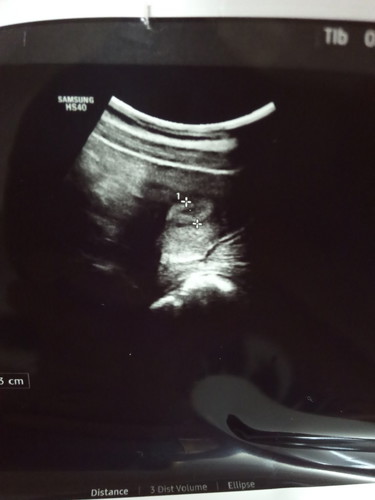

Saya patut makan apa lagi utk hilangkan loya pening ? Saya baru masuk 7weeks..Makan jeruk dah,makan asam pun dah,makan buah oren pun sudah..semua tak jalan..rasa macam bergelodak bahagian perut atas pusat. Nak kata tak cukup makan..makan saya on time..asal makan je tekak kembang,kadang lepas 1 jam makan air liur rasa macam banyak je mcm nak muntah tapi tak muntah #firstbaby #1stimemom #mommybuntu #bantusharing